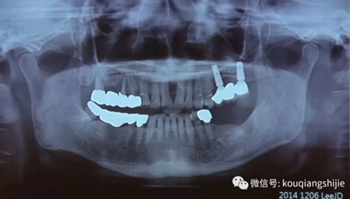

這位患者是2014年來(lái)到我們醫(yī)院

從CT上我們可以看到#14,15,17的牙槽骨被牙齒長(zhǎng)期的牙周炎破壞的非常嚴(yán)重,但是因?yàn)楫?dāng)時(shí)患者不想拔牙,所以暫時(shí)保留下來(lái)。

但是1年之后,因?yàn)榛颊邔?shí)在無(wú)法繼續(xù)使用這些牙齒

所以到我們醫(yī)院進(jìn)行了拔牙

9周后,我們發(fā)現(xiàn)黏膜組織愈合的非常好

11周翻開(kāi)黏膜,我們發(fā)現(xiàn)形成的骨已經(jīng)完全滿足我們種植的需要

我們正常進(jìn)行種植,并在縫隙處放置骨粉。